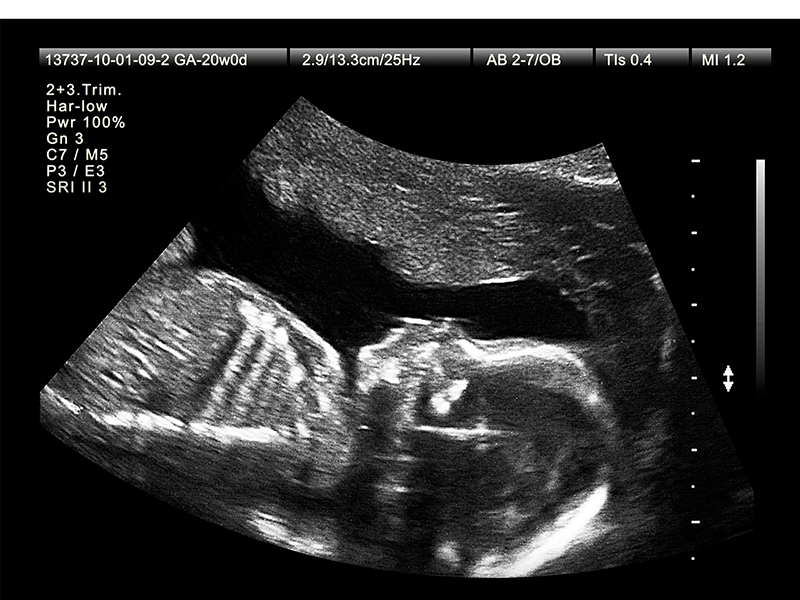

Siêu âm là phương pháp chẩn đoán hình ảnh không xâm lấn, sử dụng sóng âm thanh tần số cao xuyên qua cơ thể và phản xạ trở lại chuyển thành những hình ảnh được hiển thị trên màn hình, giúp bác sĩ chuyên khoa theo dõi và đánh giá chi tiết cấu trúc bên trong.

Vào tuần 18 - 22 của thai kỳ, siêu âm có tác dụng khảo sát hình thái thai nhi, giúp bác sĩ phát hiện thai nhi có dị tật bẩm sinh hay không.